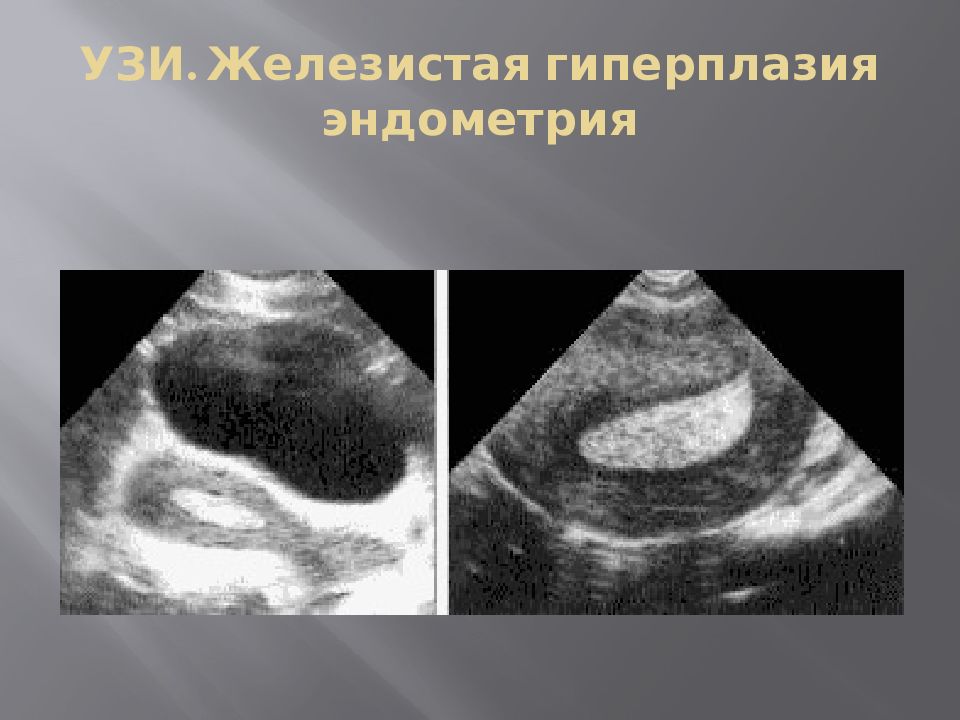

Медицинская диагностика: Гиперплазия эндометрия на УЗИ